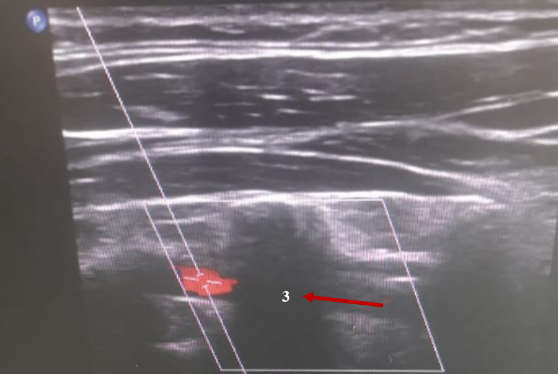

Доплерография почечных артерий и вен (рисунок 3). Внутрипочечный кровоток равномерный, прослеживается до капсулы. Индекс почечной артерии Ао = 0,9. Чётко прослеживается рисунок ветвей ренальных сосудов всех порядков до кортикальных фрагментов включительно, диаметр их не изменён, пульсация сохранена.

Рис. 3. Доплерография почечных артерий и вен. Патологических изменений не выявлено

Fig. 3. Dopplerography of renal arteries and veins. No pathological changes were detected

Заключение. Гемодинамически значимых стенозов почечных артерий не выявлено. Почечные вены проходимы с двух сторон.